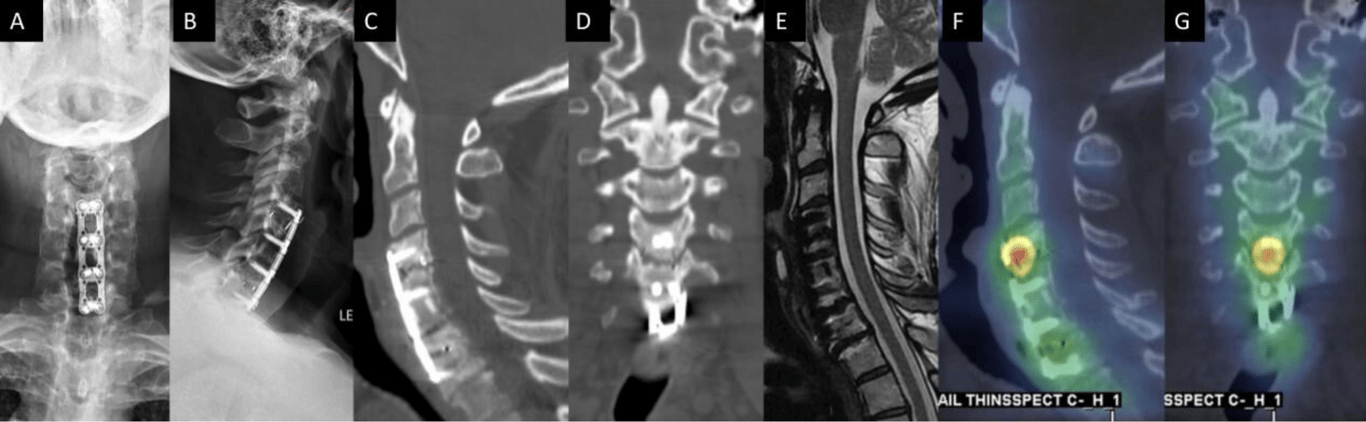

A 54-year-old man presented with persistent axial mechanical neck pain after previously undergoing C4-7 anterior cervical discectomy and fusion 2 years earlier. Anteroposterior (A) and lateral (B) plain films demonstrated all implants from the index surgery were appropriately positioned. Sagittal (C) and coronal computed tomography (CT) reconstructions did not demonstrate any bridging bone across the C4-5 disc space. No residual/recurrent central stenosis was seen on mid-sagittal T2-weighted magnetic resonance imaging (E). Sagittal (F) and coronal (G) single photon emission CT with CT images demonstrated increased radiotracer uptake at the C4-5 level, which suggested symptomatic pseudarthrosis. The patient subsequently underwent posterior cervical instrumented fusion with good result.